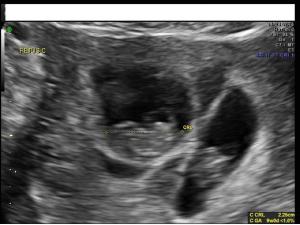

While several fetal anomalies can be diagnosed early in the pregnancy, second-trimester ultrasound can identify or exclude even more conditions. The second slideshow of our ultrasounds collection includes the second-trimester anomalies of the body and limbs that shouldn't be missed.